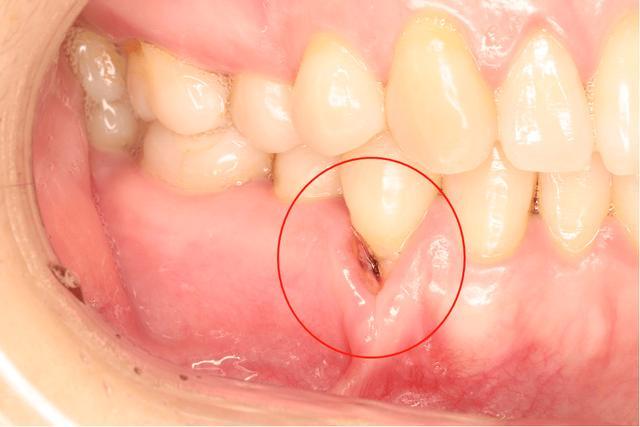

牙周炎是牙周組織的炎癥,主要影響牙齒周圍的支持結(jié)構(gòu),包括牙齦、牙周膜和牙槽骨,牙周炎的嚴(yán)重程度不同,可能從輕微的炎癥到嚴(yán)重的感染不等。

牙周炎的癥狀

1、牙齦紅腫:牙周炎患者的牙齦組織通常會變得紅腫。

2、牙齦出血:刷牙或咬硬物時容易出血。

5、牙齒松動:炎癥嚴(yán)重時,可能導(dǎo)致牙齒松動。